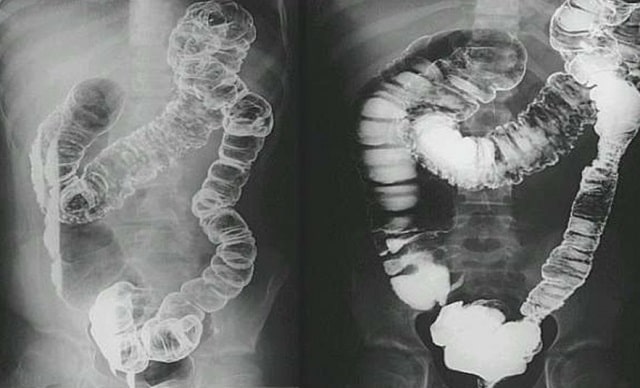

Чаще всего при болезни Крона поражаются подвздошная, толстая и прямая кишка. Верхний отдел желудочного тракта, начиная с пищевода, воспаляется реже. Однако, могут быть трудности с глотанием во время приема пищи и кровотечения в верхних отделах пищеварительной системы.